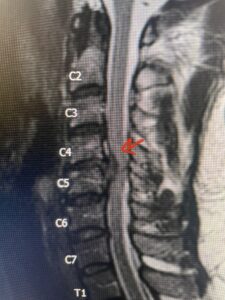

Fig 2a Sagittal and axial T2 weighted cervical MRIs demonstrating large C4 5 herniated disc with spinal cord compression red arrows

This 47-year-old male who four months prior was lifting weights developed sharp pain in his neck. After that he developed progressive numbness in his arms, neck pain and headache. He said that the right arm was worse than the left. On examination the patient had long tract weakness on the right side which included his triceps, finger extensors, hip flexors, and dorsiflexors. The patient did not have hyperreflexia. MRI (Fig. 2) demonstrated a massive, extruded disc herniation with severe cord compression. The patient because of progressive myelopathy and spinal cord compression was indicated for anterior cervical discectomy and fusion at C4-5 (Fig. 3). Patient had significant improvement of weakness and numbness post operatively.

Fig. 2a Sagittal T2-weighted cervical MRI demonstrating large C4-5 herniated disc with spinal cord compression (red arrow)

Fig: 2b Axial T2-weighted cervical MRI demonstrating spinal cord compression from C4-5 herniated disc (red arrow)